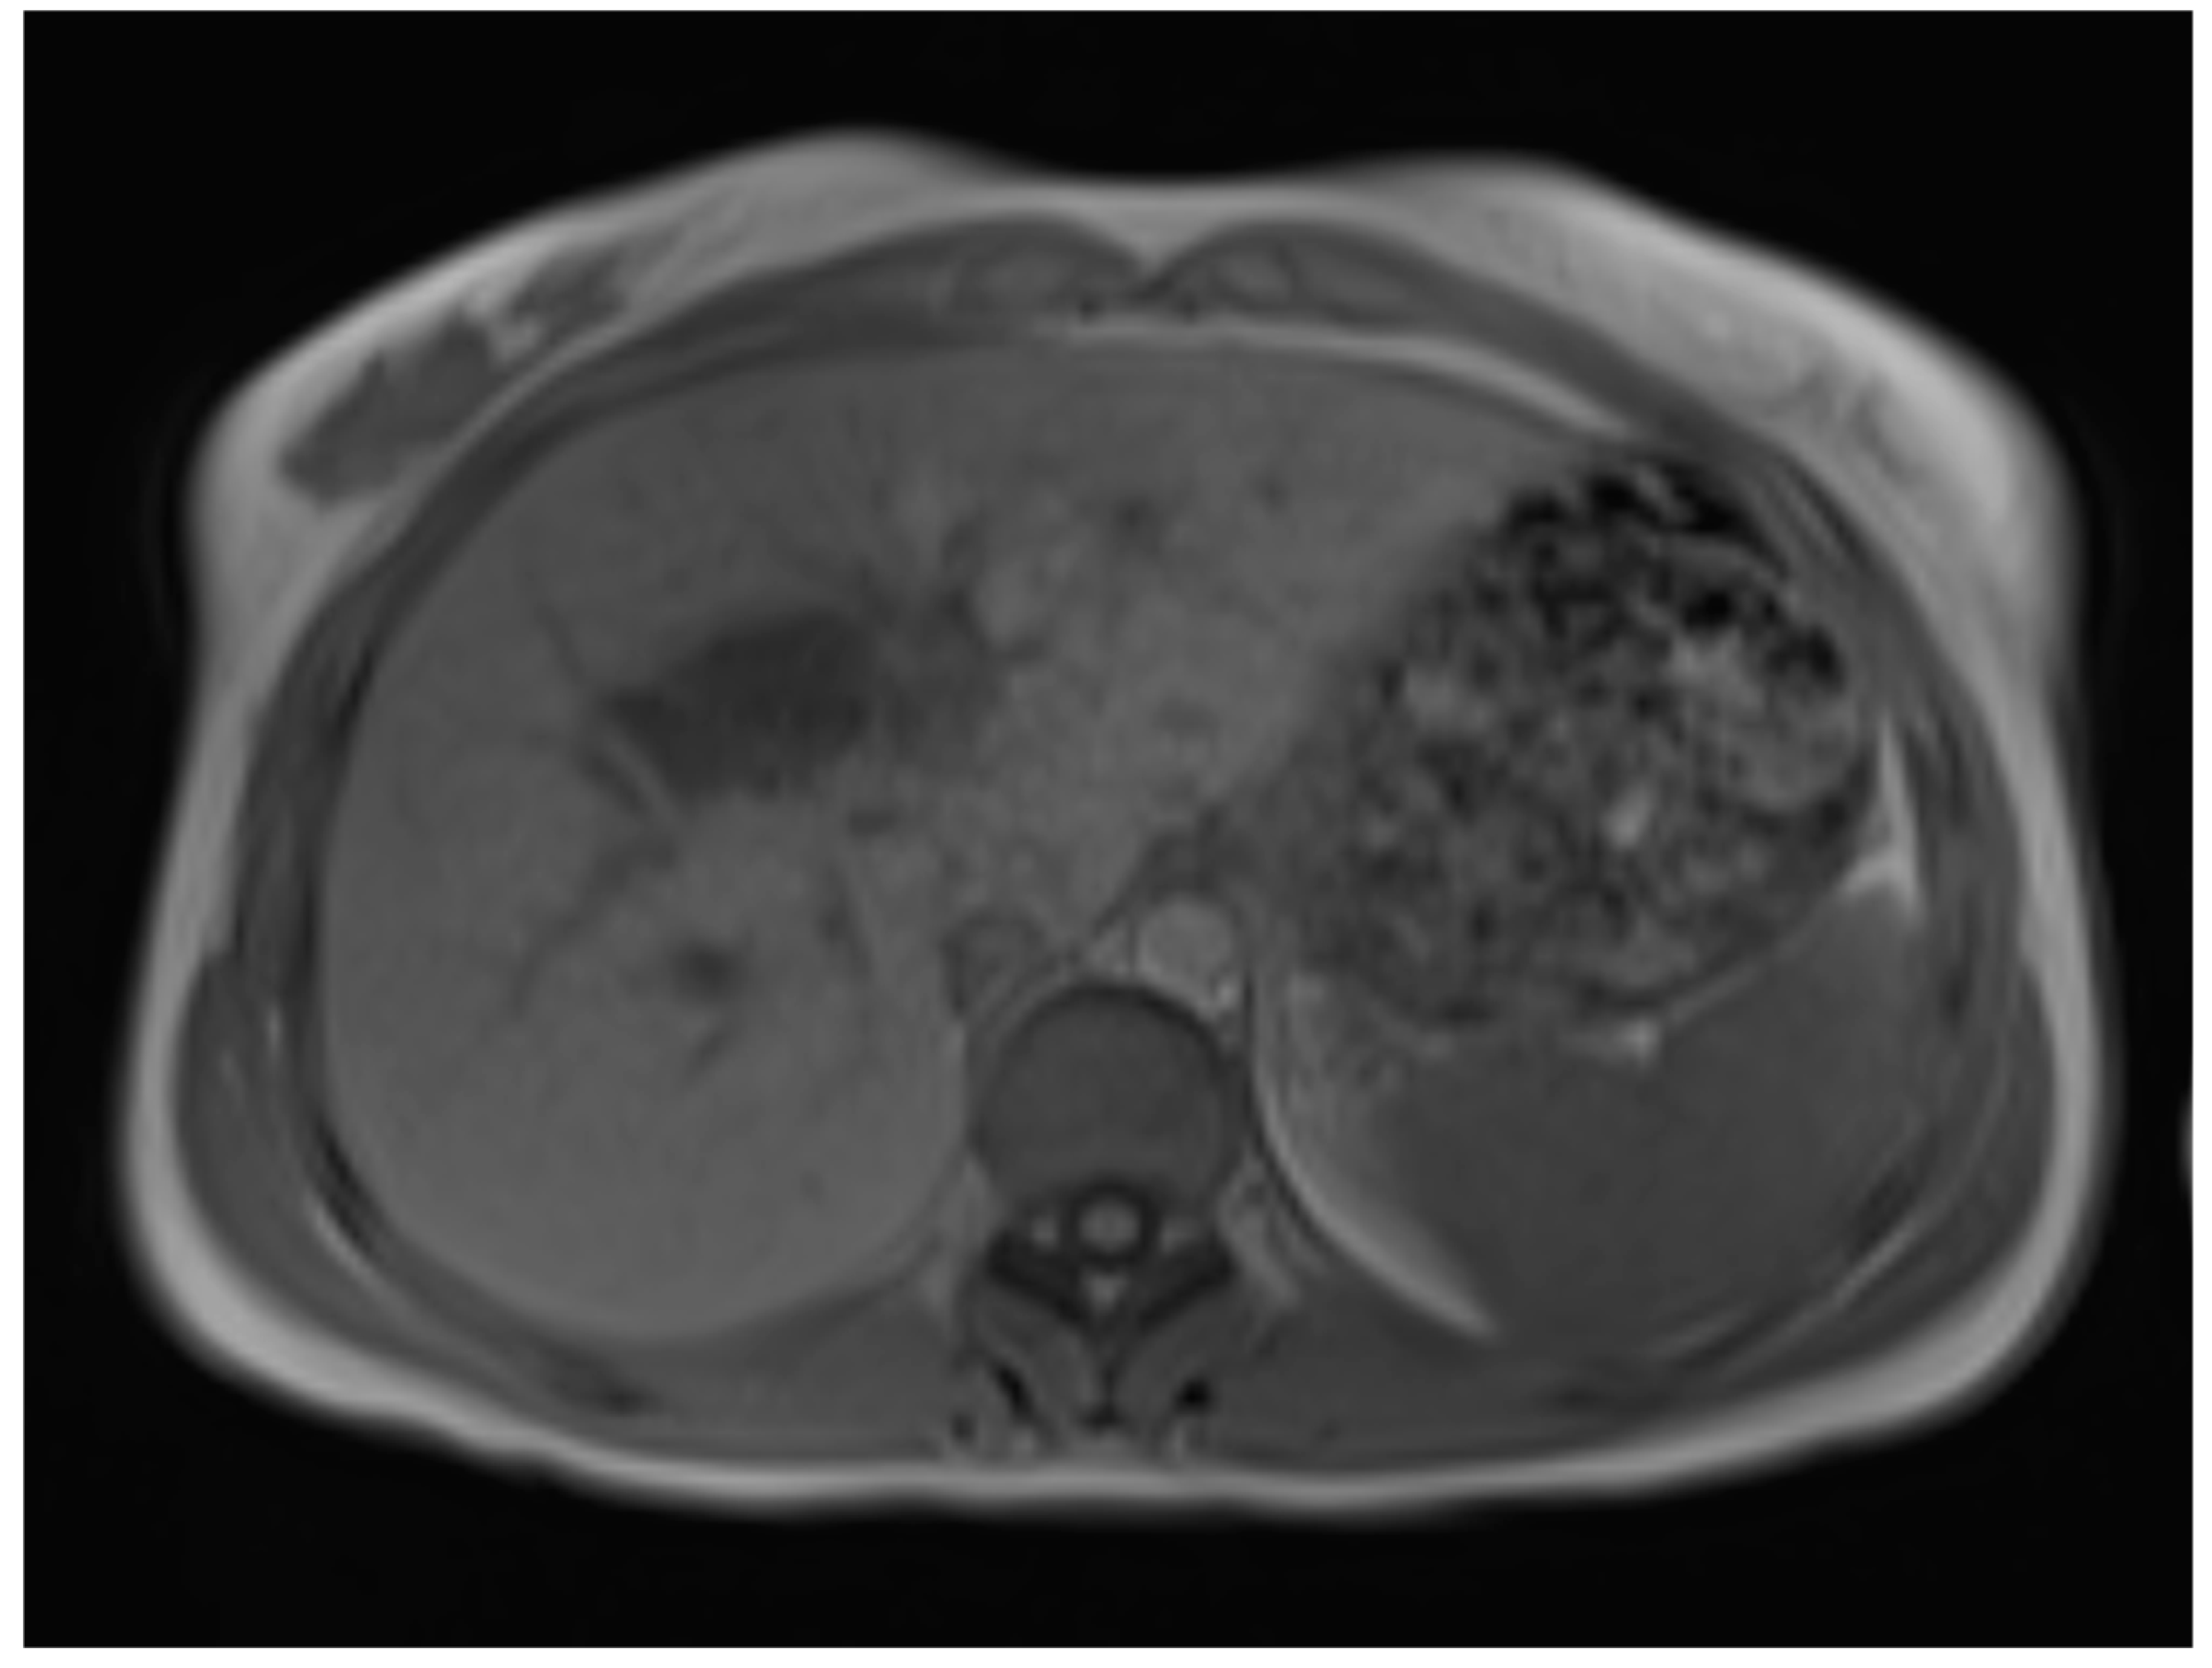

A liver MRI scan confirmed a cystic structure with multiple daughter cysts, hypointense on a T1-weighted image (T1WI), and hyperintense on a T2-weighted image (T2WI), with no solid components, no signs of membrane rupture, and a maximum diameter of 10 cm (craniocaudal) (Figure 1). Additionally, elevated signals on T2WI in the surrounding liver tissue were found. The T1 sequences did not reveal any contrast uptake after 5 (Figure 2), 10, or 20 (Figure 3) minutes post-injection. Furthermore, DWI/ADC mapping indicated a hydatid cyst. The DWI sequences included a trace DWI (Figure 4), an ADC map (Figure 5), and both at b800. Radiomics and AI tools were not involved. The trace DWI showed an area of hypointensity in the region of the cyst that was surrounded by a hypointense layer, depicting the cystic wall. The ADC map revealed hyperintensity within the area, in concordance with a typical depiction of cysts on an MRI scan.

Figure 2.

First MRI scan: Axial T1W MRI scan showing hypointense daughter cysts in liver segment IV with no contrast uptake after 5 min.

Figure 3.

First MRI scan: Axial T1W MRI scan depicting hypointense areas in liver segment IV, suspicious of daughter cysts, with no contrast uptake after 10 min.